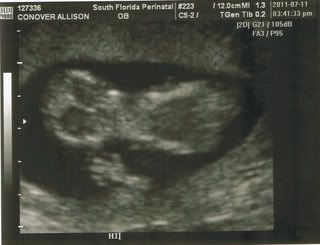

On Monday, Brian, Mom, Kelly, Sterling, and I went to see little peanut most for the 1st time in person. When the tech started, peanut was jumping around in there like a little "mexican jumping bean" - I say he/she was using my bladder as a trampoline! He/she wouldn't cooperate, turning every way except the way the tech wanted him/her to. Then all of a sudden he/she turns to face us and waves!

Photobucket

It was the cutest thing! Then he/she went back to being stubborn. I was sent to the bathroom then had to flip from left side to right side, sit up, lay back down, repeat - NOTHING. I kept reminding Brian that this was certainly HIS child! Then he/she stops moving, all we could see was his/her little heart beating. I guess he/she was tired from all that jumping around!